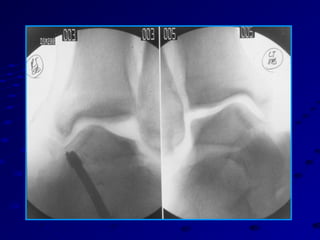

TALAR TILT TESTINGTALARTILT TESTING ANKLE NEUTRAL OR SLIGHTLYANKLE NEUTRAL OR SLIGHTLY PLANTAR FLEXEDPLANTAR FLEXED VARUS STRESS APPLIED AT CCVARUS STRESS APPLIED AT CC JOINTJOINT 9-10 DEGREES = + STRESS TEST9-10 DEGREES = + STRESS TEST 3-5 DEGREES SIDE VS SIDE = +3-5 DEGREES SIDE VS SIDE = +

ANTERIOR DRAWER TESTANTERIORDRAWER TEST ANKLE IN SLIGHT PLANTARANKLE IN SLIGHT PLANTAR FLEXIONFLEXION AVOID FALSE NEGATIVE FROMAVOID FALSE NEGATIVE FROM DELTOIDDELTOID 9-10 MM = + TEST9-10 MM = + TEST 3-5 MM SIDE VS SIDE = + TEST3-5 MM SIDE VS SIDE = + TEST